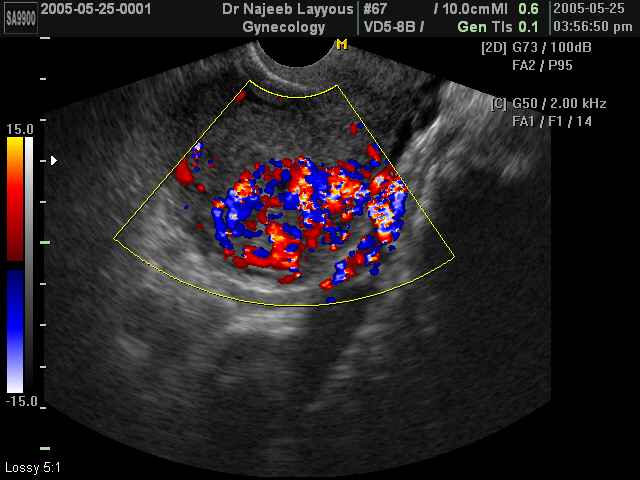

صور طبية للحمل بجهاز الالتراساوند | الدكتور نجيب ليوس